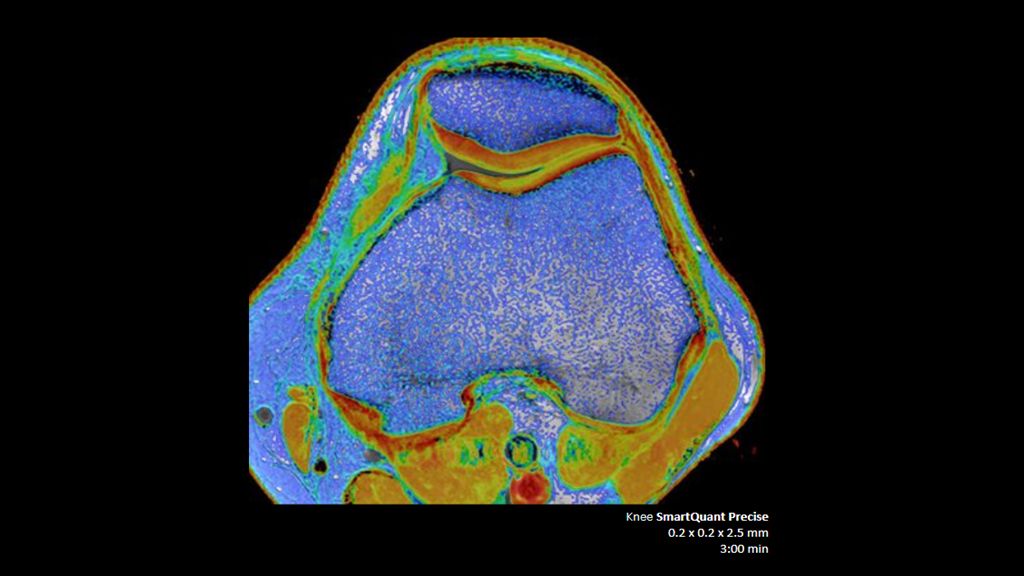

2. Reconstruction technology Compared to conventional (SENSE/ Compressed SENSE, SmartSpeed AI) imaging. Sharpness was evaluated with phantom scanning.